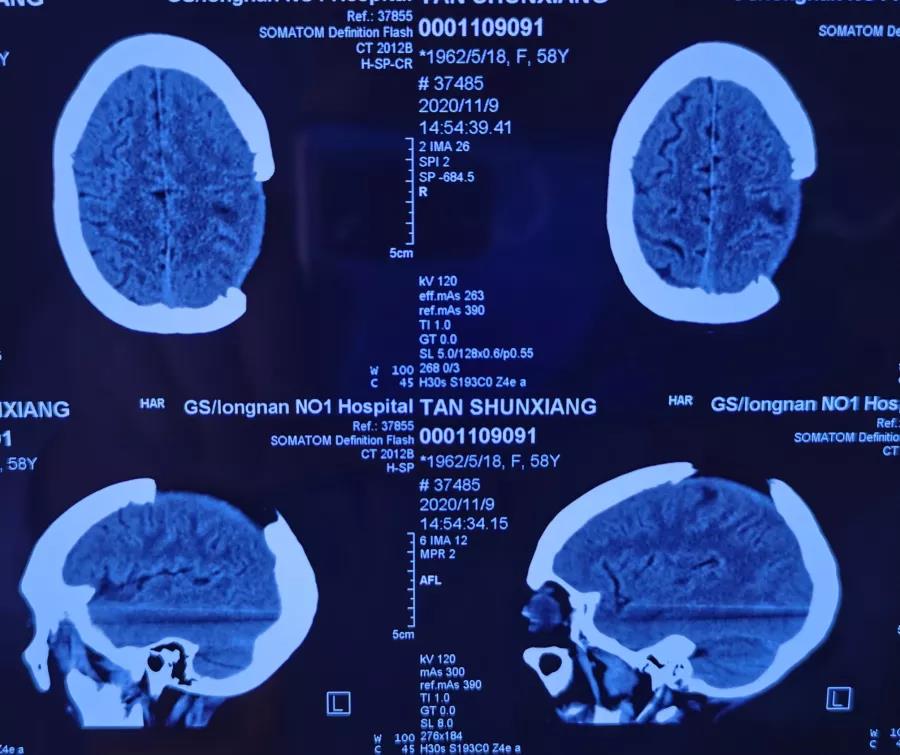

患者,58岁,渐进性头疼1年余,遂来我院就诊。入院后行头颅CT、MR示左侧顶叶占位性病变,经接诊医师李明详细说明病情后家属决定于我院进行手术治疗。

副主任周小荔积极组织全科医师慎密讨论,研究分析后认为病变系颅内重要功能区脑膜瘤。为避免损伤造成患者相关功能障碍,医师团队精心设计了手术方案,全面细致考虑了手术中可能出现的每一个环节,并进行了反复论证,最后确定了手术方案。明确手术方案后,由副主任医师李明主刀,主治医师谈小红、住院医师祁军强担任助手进行手术,肿瘤及被肿瘤侵蚀硬膜、颅骨成功切除,手术顺利。